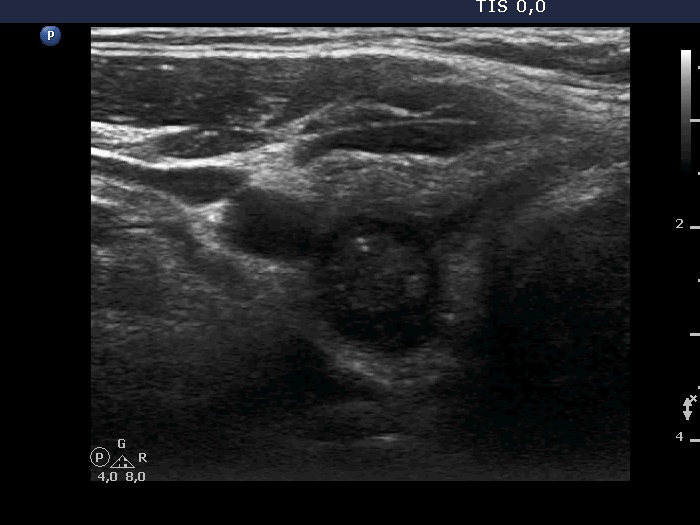

Second examination 2 years later (2nd row of images)

Clinical presentation. The patient had no complaints. The endocrinologist colleague noticed a significant increase in the size of the nodule on repeat ultrasound and he sent the patient for a repeat FNA.

Palpation: no abnormality.

Ultrasonography. The pattern was essentially the same. The only difference concerned the lesion in the dorsal part of the right lobe which clearly increased in size. Moreover, it became more obvious that the lesion had microcalcifications.

Aspiration cytology of the lesion resulted in Hashimoto's thyroiditis.